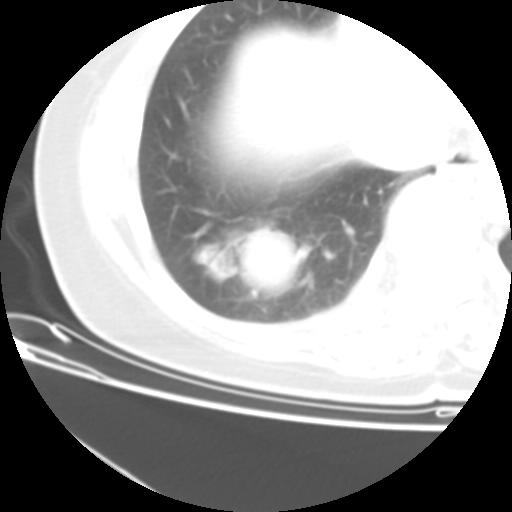

右肺下叶类癌

女 46岁,咳嗽咳血10月

【linyiming】右肺下叶见类圆形软组织影,边缘欠规整,略分叶状。考虑炎症假瘤可能?

未排除周围型肺癌。建议CT增强。

【aosangwa】肺癌的主要特征是:毛刺征、分叶征及胸膜凹陷征,此病例位于右肺下叶距胸膜很近,但没有胸膜凹陷征,其周围像示渗出性病变,病灶在两窗上没有大小没有发生大小改变。

考虑其良性肿瘤,炎性假瘤可能性大,其主要鉴别是:结核球、周围型肺癌、血管瘤

病理诊断类癌(周围型)。